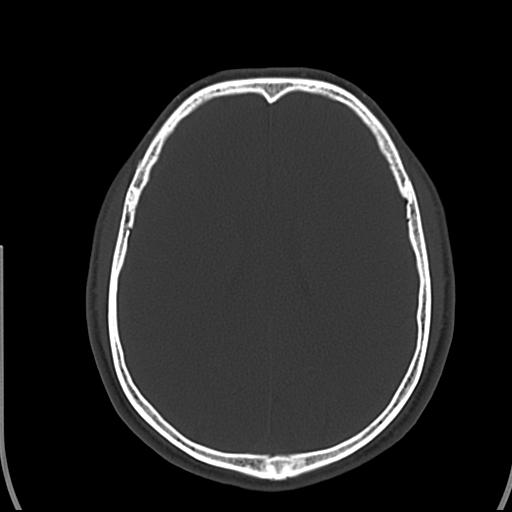

标题: CT25435:头皮下高密度影???

头皮下高密度结节影???临床上在老年男性比较常见。大家看看是什么?成因是? 本例患者,男性,51岁。外伤来诊。无染发史及发根植入史。